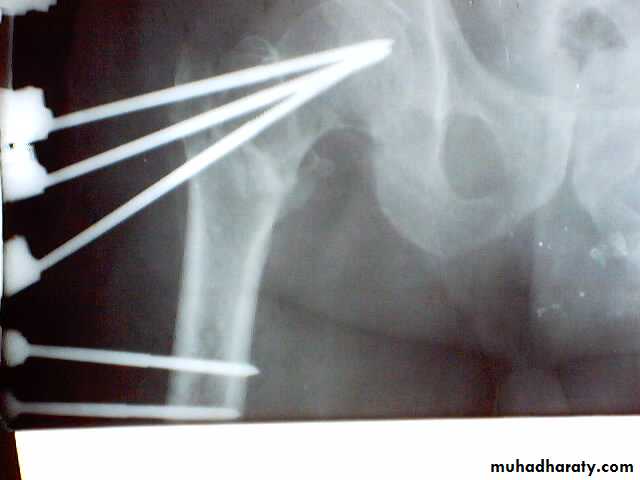

1.Sliding nail

2.L-plate

3.External fixation

Gamma nail